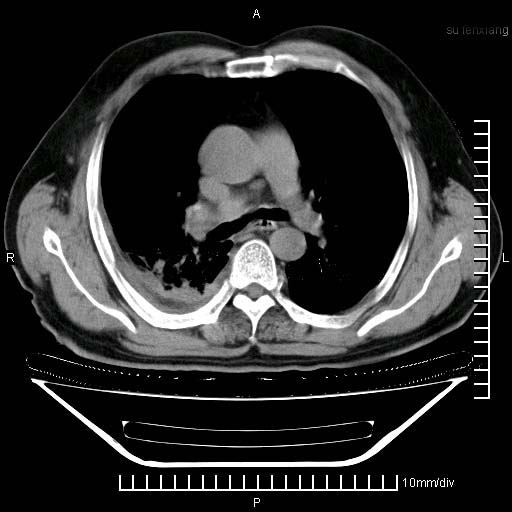

标题: CT24043:胸部增强:男性,60岁

既往肺结核,近10几天,咳嗽,咳痰,右侧胸痛,疼痛较明显,右上肺斑块考虑结核灶胸膜粘连,增强,可惜动脉期没有定好,未见强化,可延迟4分后又见较明显强化,中心见低密度影,如果说结核是边缘强化,可这个灶强化的面积挺大的,让人很挠头。

延迟4分后

[img][/img]